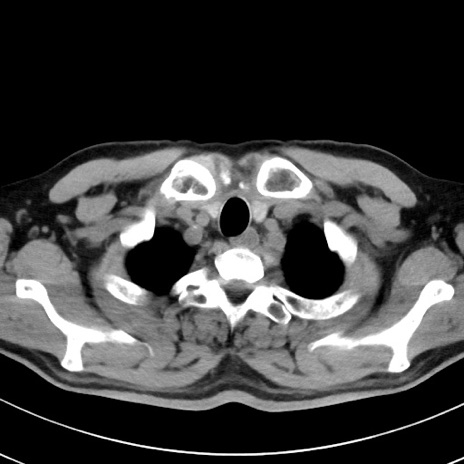

【腹部TIPS】症例29 参考症例 CT(横断像)

症例

70歳代男性